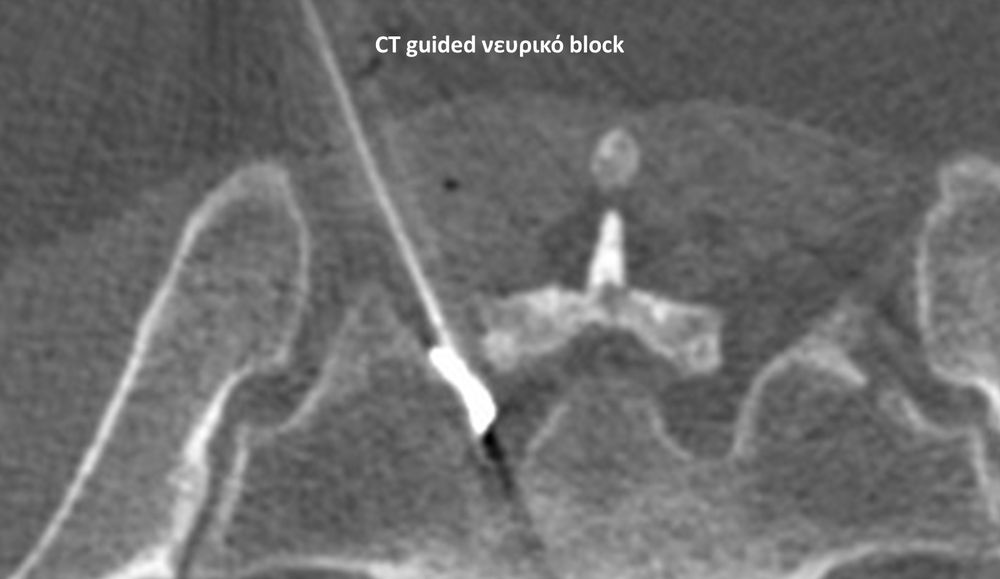

Με την βοήθεια της επεμβατικής ακτινολογίας είναι δυνατόν να πραγματοποιηθούν διαφορες ενέσιμες τεχνικές που αποσκοπούν στη μείωση του μυοσκελετικού πόνου, την ενίσχυση της αποτελεσματικότητας της φυσιοθεραπείας και την επιτάχυνση της διαδικασίας επούλωσης. Οι τεχνικές αυτές περιλαμβάνουν την κατευθυνόμενη έγχυση φαρμάκων ή πραγματοποίηση θεραπευτικών χειρισμών ακριβώς στη θέση τηςπαθολογία. Ετσι εξασφαλιζεται η μέγιστη αποτελεσματικότητα ( έως 95% κατά περίπτωση) και ασφάλεια σε σχέση με τυφλούς χειρισμούς χωρίς ακτινολογική καθοδήγηση.